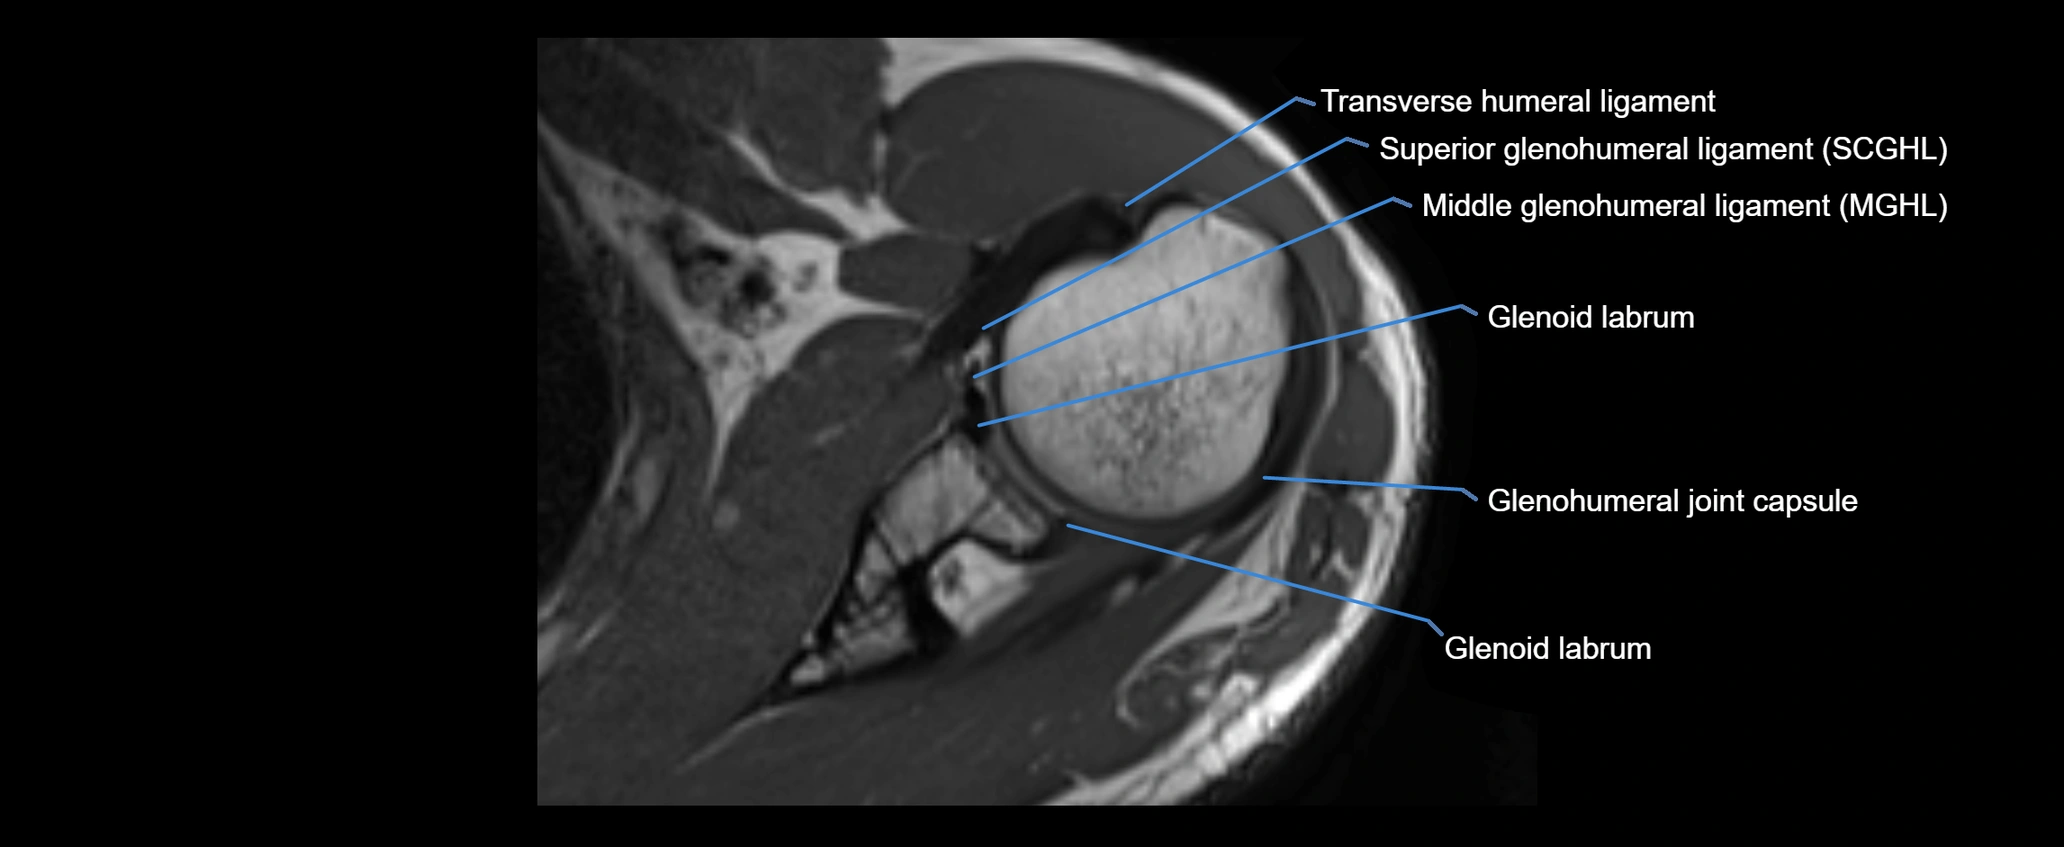

MRI images

image